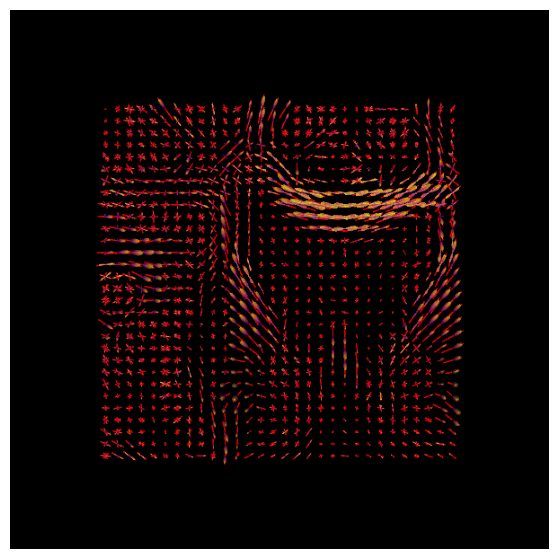

With DIPY’s peaks_from_model the peak directions (maxima) of the ODFs can be found. We will visualize both the ODFs and peaks in the same space:

csd_peaks = peaks_from_model(model=csd_model,

data=data_small,

sphere=default_sphere,

relative_peak_threshold=.5,

min_separation_angle=25,

parallel=True,

num_processes=10)

scene.clear()

fodf_peaks = actor.peak_slicer(csd_peaks.peak_dirs, peaks_values=csd_peaks.peak_values)

scene.add(fodf_peaks)

fodf_spheres.GetProperty().SetOpacity(0.6)

scene.add(fodf_spheres)

csd_both = window.snapshot(

scene, fname=os.path.join(os.getcwd(), 'csd_both.png'), size=(600, 600),

offscreen=True)

fig, axes = plt.subplots(figsize=(7,7))

axes.imshow(csd_both, cmap="plasma")

axes.axis("off")

plt.show()